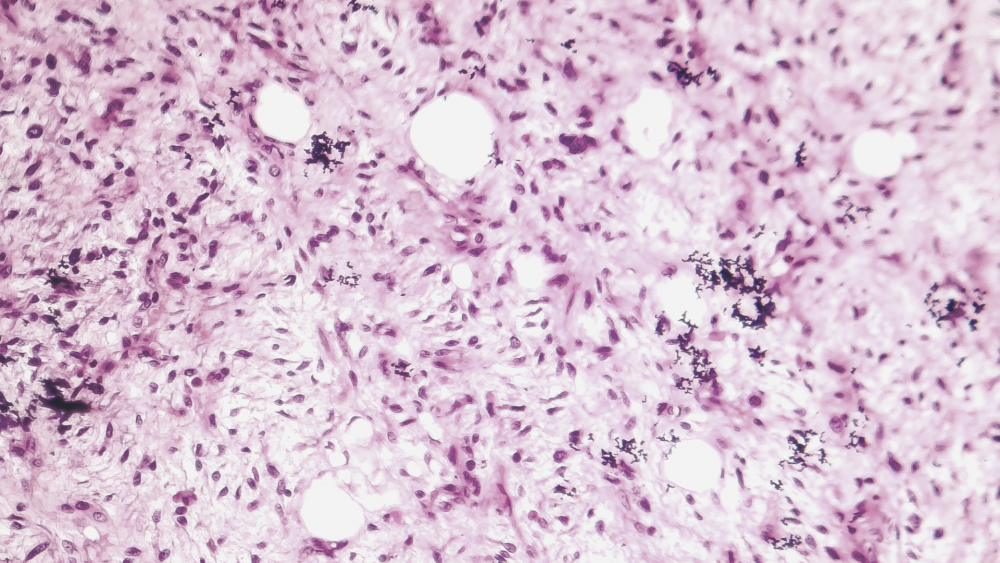

Саркомы мягких тканей головы и шеи

Саркома мягких тканей (СМТ) — это злокачественное новообразование, развивающееся из клеток внескелетной соединительной ткани, к которой относятся все анатомические образования между скелетом и кожей: мышцы, жировая ткань, сухожилия, связки и т. д.).